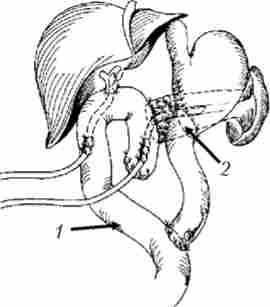

Сполучення жовчного міхура з тонкою кишкою (операція Монастирського) виконується при прохідному протоки міхура. Операція технічно нескладна і малотравматичні, але істотний її недолік - небезпека розвитку рецидиву жовтяниці при проростанні пухлиною протоки (рис. 21.14).

Холецістоеюноанастомоз з міжкишкових анастомозу але Брауну

Мал. 21.14. Холецістоеюноанастомоз з міжкишкових анастомозу але Брауну: